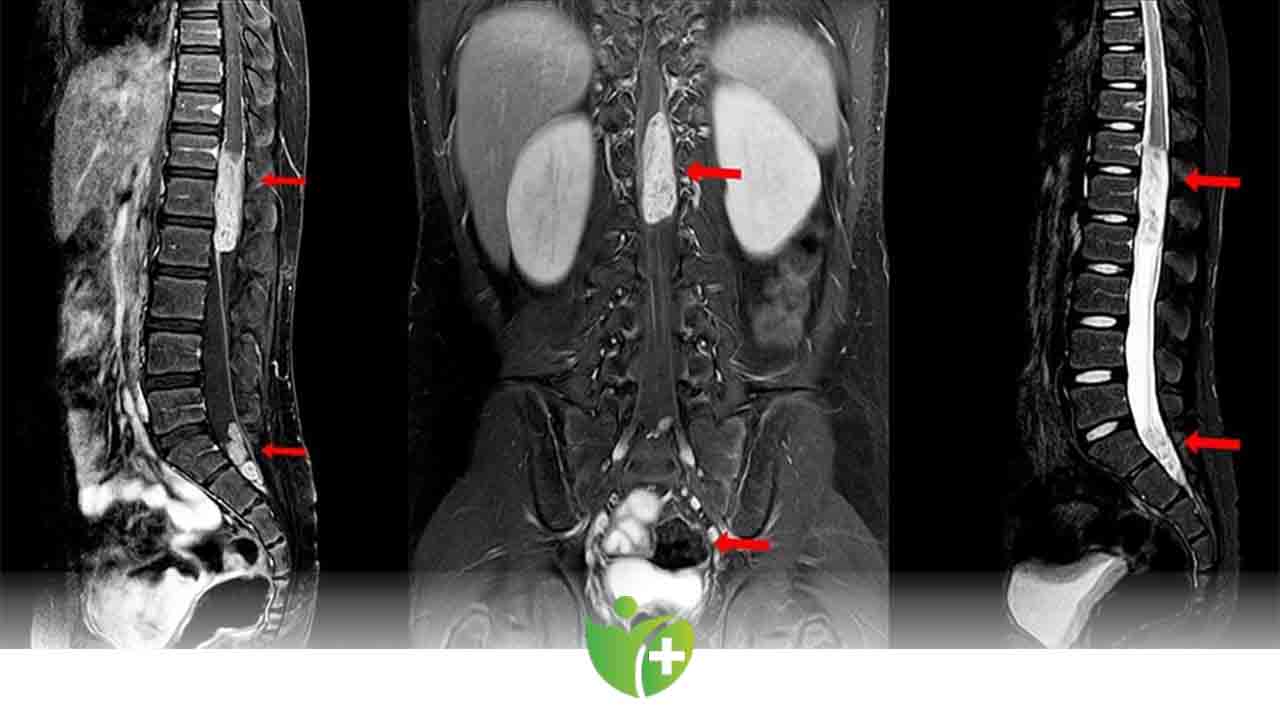

• Manyetik rezonans görüntüleme (MRG). MRG, omurga, omurilik ve sinirlerinizin doğru görüntülerini üretmek için güçlü bir mıknatıs ve radyo dalgaları kullanır. MRG genellikle vertebral tümörleri teşhis etmek için tercih edilen testtir. Belli dokular ve yapıları vurgulamaya yardımcı olan bir kontrast madde, test sırasında ayağınızdaki veya önkoldaki bir damar içine enjekte edilebilir.

Metastatik hastalarda başka bir omurga lokalizasyonunda da lezyon olabilme ihtimalinden dolayı (%15) görüntüleme yöntemleri tüm omurgayı içerecek şekilde çekilmelidir.